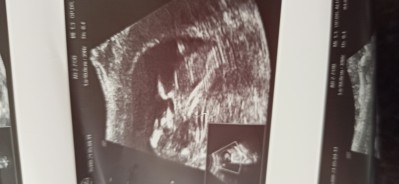

Cinsiyet tahmınınız varmı kızlar :)  12 hafta 4 gün

Gebelik haftası 12 hafta 4 gün

Kafa yapısı erkek gibi geldi bana :)

Erkek annesi aynı. Benim oğluşum gibi duruşu var

Kafası asagidaimage